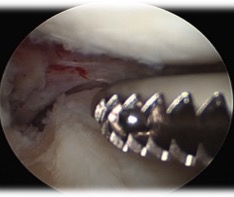

- insert graft bone into slot

- secure with screw

- flip meniscus

- secure posterior horn with all inside sutures, body with inside out, anterior horn with outside in